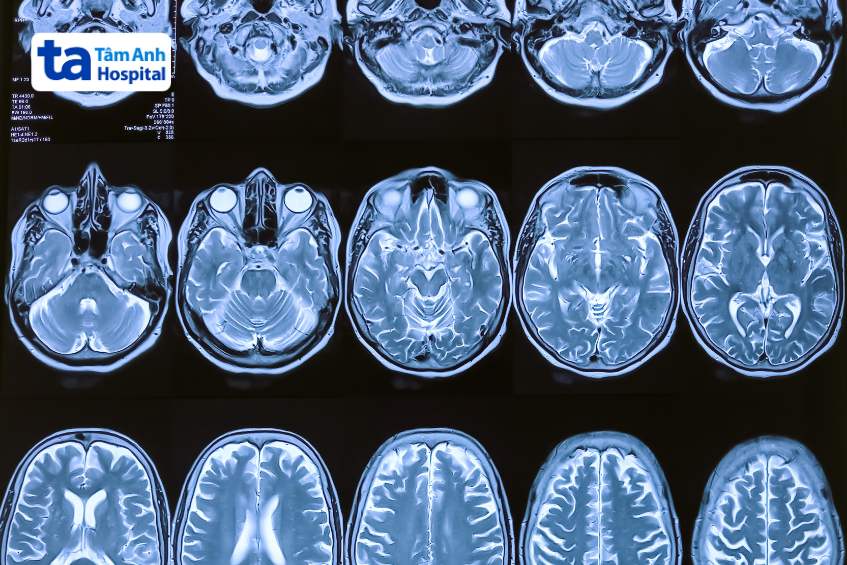

Teo não ở người trẻ tuổi là tình trạng mất tế bào não, giảm thể tích não và khả năng kết nối giữa các nơron trong não xảy ra ở người trẻ tuổi. Bệnh lý này mang những đặc trưng liên quan đến mức độ suy giảm nhận thức, tương quan với một số thay đổi về hình thái của não, bao gồm: vỏ não mỏng, giảm thể tích chất trắng và chất xám, não thất to và mất hoặc giảm hiện tượng hồi hóa (gyrification).

Để chẩn đoán bệnh teo não, trước tiên, bác sĩ sẽ kiểm tra sức khỏe tổng thể, sau đó chỉ định người bệnh thực hiện một số cận lâm sàng sau đây: